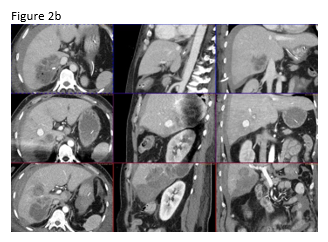

A 49 year old patient was admitted to the hospital for sepsis and shock of unknown origin. The patient presented with signs of sepsis and hemodynamic instability that justified an urgent approach including complex intensive care and intubation. Bedside ultrasound (US) found ascites and an abscess in the right liver lobe (9 cm) (Figure 1a). The patient was treated with broad-spectrum antibiotics and puncture and drainage of the abscess (Figures 1 a-c and 2 a-b). In addition, a biopsy was taken from the periphery of the lesion. A few days after the removal of the drainage the patient presented with a progressive elevation of liver enzymes. US revealed a cystic lesion measuring 30 mm that was proximal to the drained abscess (Figure 1a). Color Doppler Imaging (CDI) showed arterial flow inside the lesion, and contrast enhanced ultrasound (CEUS) showed early arterial enhancement and turbulent flow with a “to-and-fro” sign, suggestive of a pseudoaneurysm (Figure 1b). There was also a heterogeneously vascularized lesion with enhancing septae in the surrounding liver parenchyma (Figure 1c) . A few days later the patient presented with tachycardia and a drop of hemoglobin from 10 g/dl to 7 g/dl. US revealed spontaneous thrombosis of the pseudoaneurysm (Figure 1d) with intra - and perihepatic hemorrhage (Figure 1e).

Figure 2: Computed tomography (CT)showed abscess formation before drainage and perihepatic ascites (a). Twelve days after drainage removal a CT follow-up showed hyperenhancing intrahepatic lesion in proximity of the abscess, suggestive of a pseudoaneurysm (b). CT confirmed the spontaneous thrombosis of the pseudoaneurysm (c).